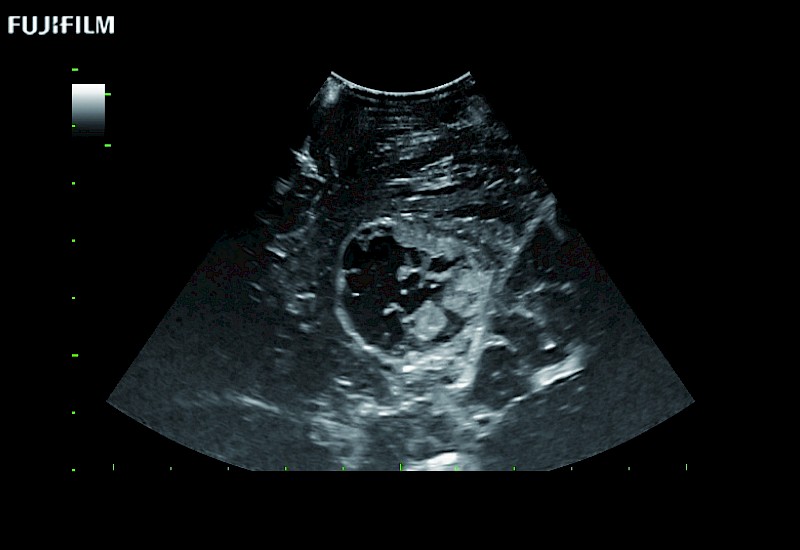

Tight curved (12mm) array transducer that is ideal for scanning during cranial guidance procedures.

Main Specifications:

Smaller footprint (20mm) curved array transducer that is ideal for scanning during cranial guidance procedures.